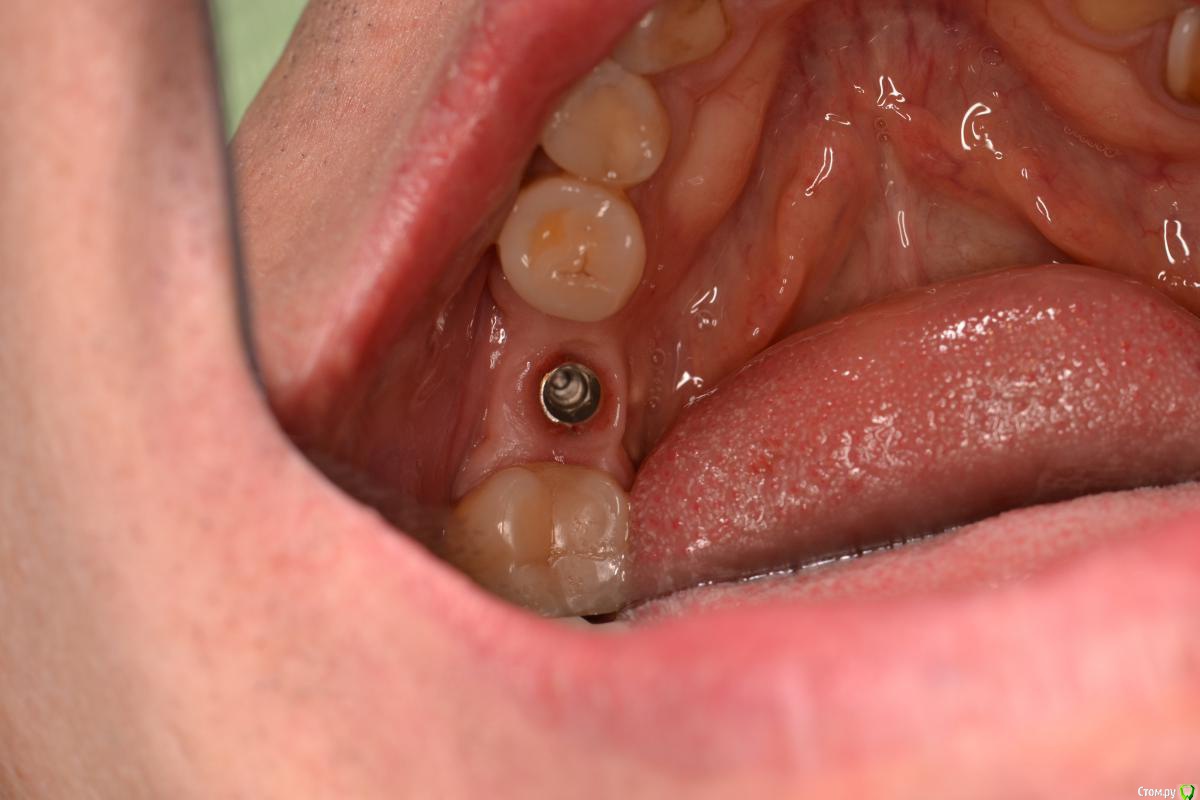

TIGER Опубликовано 22 декабря, 2016 Поделиться Опубликовано 22 декабря, 2016 Если вам сегодня нравится,что вы сделали вчера ,то вы стоите на месте....)Имплант ставил я, с виду по первому фото видно,что вроде-бы ничего...но на тот момент я бы был удовлетворён результатом,да он интегрирован,пациент доволен,отпротезировал бы,но сегодня нет...зондирование выявило резорбцию....и главное я знал,что прогноз не очень,эстетика и жизнь этого болтика...настоял на удалении...сегодня заказал набор,и на выход,сразу же имплант,заглубил,как надо)Как говорил если мне не изменяет память Эдуард Анчаков наступает эра вынимайзинга....начал со своего)P.S какое приятное чувство когда ты можешь исправить свои недочёты) 3 Ссылка на комментарий

TIGER Опубликовано 22 декабря, 2016 Автор Поделиться Опубликовано 22 декабря, 2016 Почему такое могло произойти,есть снимки после установки?Недозаглубил...банально...Снимка нет Ссылка на комментарий